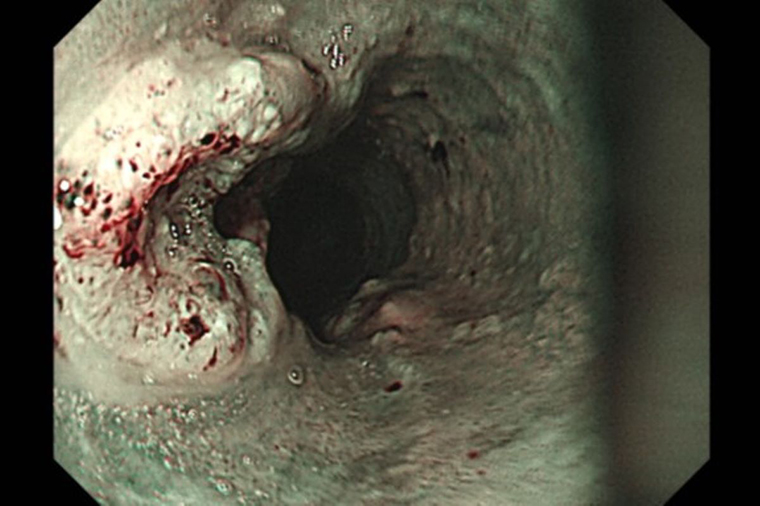

▲胃鏡檢查是診斷食道癌最常使用的方法,圖片為胃鏡影像下的食道內側,左側突起處為癌症病灶。(圖/台北慈濟醫院提供)

胃鏡檢查是診斷食道癌最常使用的方法,可直接觀察腫瘤並進行切片確認,同時搭配電腦斷層、全身骨掃描、腦部磁振造影、全身正子攝影等評估轉移情形。洪嘉聰表示,食道癌治療會依期別與病灶範圍調整,但手術切除仍是首要考量。傳統開胸手術需於胸腹切開約15~20公分大的傷口,且易併發肺炎;若合併下咽癌,可能得進一步施行全喉切除與永久氣切,造成語音、進食與呼吸功能的永久改變。現今微創技術則可透過胸腔鏡與腹腔鏡完成,過程只需在胸腹部開數個1~2公分的小切口,並於頸部開4~5公分的切口進行胃管上拉及頸部食道縫合重建,術後恢復較快,併發症風險也相對降低。